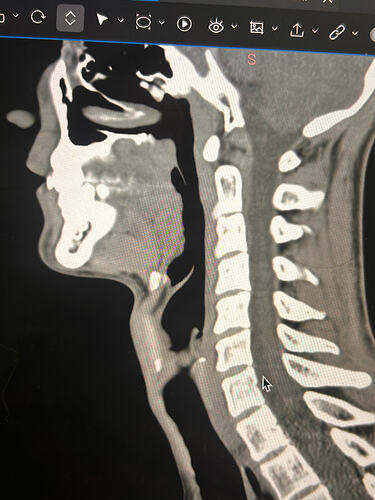

Here are some of my 2-d scans, thanks. The top one is my right greater horn and the bottom is the left

Thank you for the additional images. After reading @Jules observations, I went back over the first 4 images you sent & realized I’d miss some significant things. I’ve annotated more images for you below:

This one shows your right hyoid greater horn from behind.

I totally missed that I could see your whole hyoid bone from the front in this image. Jules is right, your greater horns are very thick from top to bottom. You can also see that your left greater horn is pretty straight, but the right one has an upward curve to it. I’m not sure what the calcification is below your hyoid but it’s most likely thyroid since the thyroid sits just below the hyoid in the neck.

In this image, you can see the differences in the shapes of your hyoid’s greater horns. The right one is more curved but the left one is thicker in width medial to lateral. In this image from the front it looks like both greater horns may be contacting your cervical spine in certain head positions, but again, that may an illusion created by the angle of the image.

In the final two images you sent, the right greater horn is very close to your cervical spine so there’s a good chance it’s causing you some problems as well as possible carotid artery irritation or compression in different head positions. The image of the left one doesn’t show as much of the greater horn so I can’t tell how close to the spine it is. Can you back the left image out a bit so it looks more like the right one?

Do you have worse symptoms on your right side in spite of the styloidectomy?

I was trying to get an image of the whole greater horn on the left but I could only get small glimpses of it as I went through the slides. Maybe because of its shape. As far as pain on the right that is where I usually notice issues, especially the lump I feel whenever I swallow, although the left can also get very tight and painful at times.